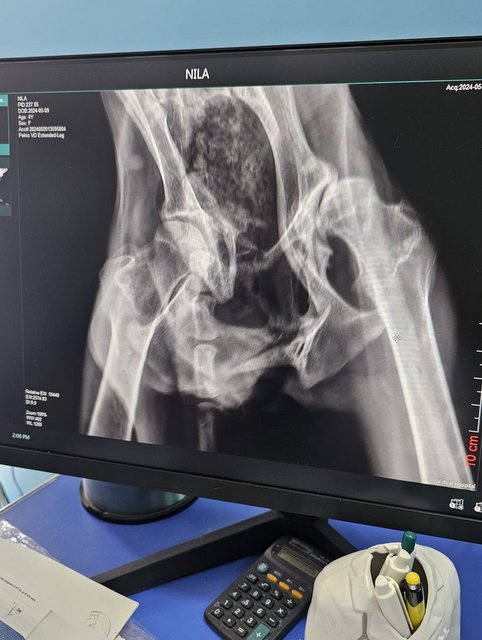

Das zerschmetterte Becken zeigt sich hier stark und dazu kommt noch der aus der Pfanne gerutschte Hüftkopf.

Nyla hat noch einen längeren Weg vor sich, sie muss Gewicht zulegen, Muskeln aufbauen und Kräfte sammeln. Wahrscheinlich wartet dann eine Operation auf sie, in der der Hüftkopf entfernt wird, da er ja sowieso nicht mehr in der Pfanne sitzt. Das zerborstene Becken muss von allein langsam heilen.

Da lag Nyla nun und kein Mensch kümmerte sich um den verletzten Hund, die, wie wir jetzt wissen, ein gebrochenes Becken und ein aus der Pfanne gerutschtes Hüftgelenk hat. Es gab Menschen, die legten ihr trockenes Brot vor die Nase. Zu mehr reichte es nicht...